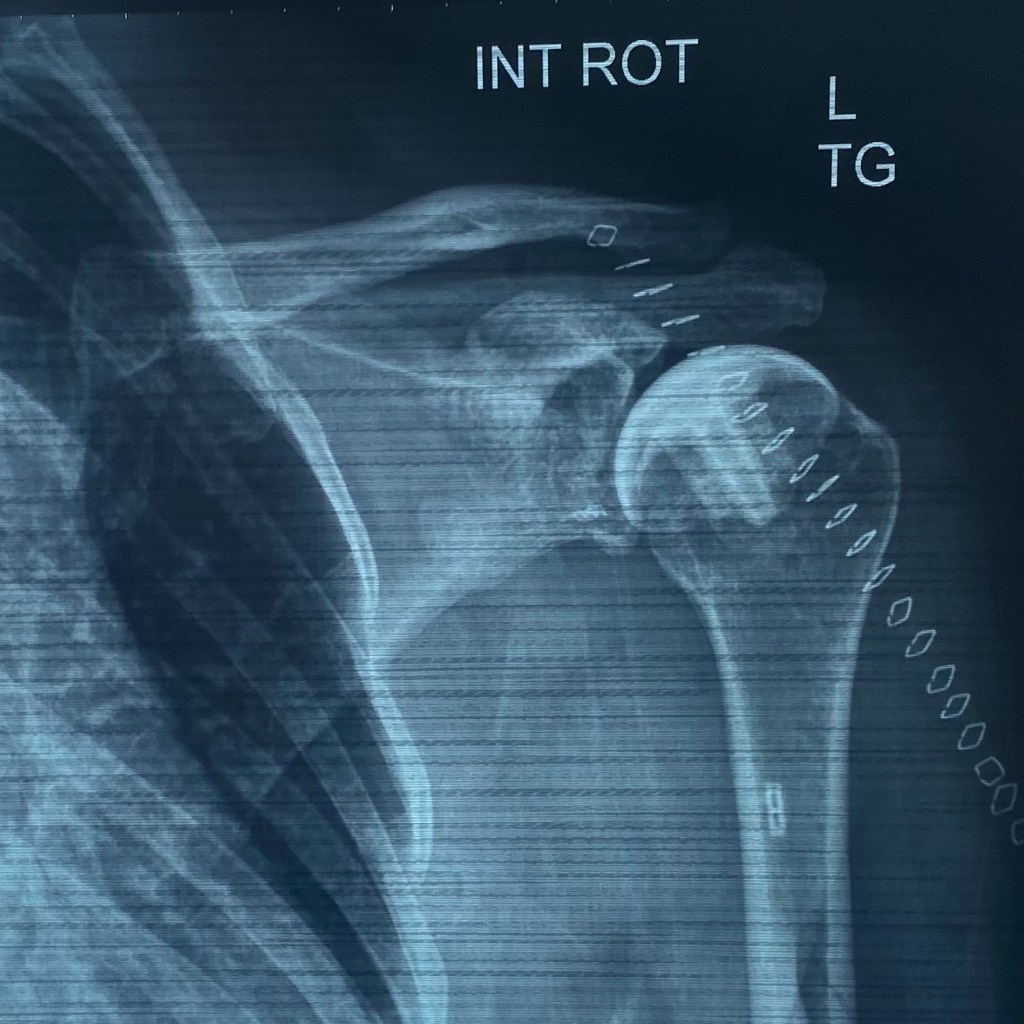

I spent hours of sleepless nights pre-surgery searching for things like “what to pack for hospital?” and finding very little that was actually helpful in anyway. I was headed for PyroTITAN Humeral Resurfacing Arthroplasty aka shoulder replacement and I was scared s***less of what was ahead of me. I didn’t know what I should be asking my surgeon and didn’t want to waste his time asking stupid questions.